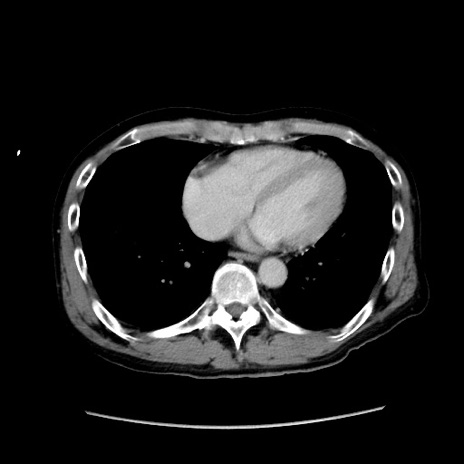

冠状断像